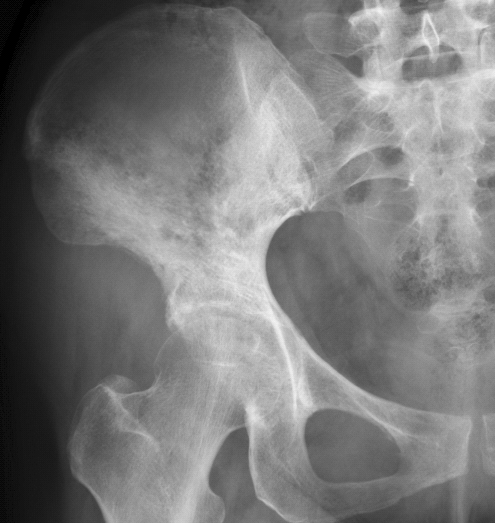

瘤软骨钙化

瘤软骨常表现为环状钙化, 是诊断软骨类肿瘤较为可靠的影像学征象。环状钙化形成于环状软骨、以及软骨小叶边缘的软骨基质。钙质沉着可呈小点状、小条状、半环状或弧形;亦可浓密相连、重叠呈菜花状。钙化环的形态和密度可反映瘤组织分化程度, 通过观察钙化环的形态和密度,有助于良恶肿瘤的鉴别。良性瘤软骨之瘤细胞分化好、生长缓慢、血供充分, 钙化环完整,密度高, 边缘清楚。良性软骨类肿瘤如骨软骨瘤(图 35)、软骨母细胞瘤(图 36)、内生软骨瘤(图 37)等均可于瘤组织内发生环形钙化。恶性瘤软骨则呈密度淡薄, 边缘模糊的不规则钙化,恶性骨肿瘤的环形钙化,最多见于软骨肉瘤(图 38),其次是骨肉瘤。CT 是发现肿瘤内软骨钙化最为敏感的检查方法。

图 38.瘤软骨钙化:软骨肉瘤